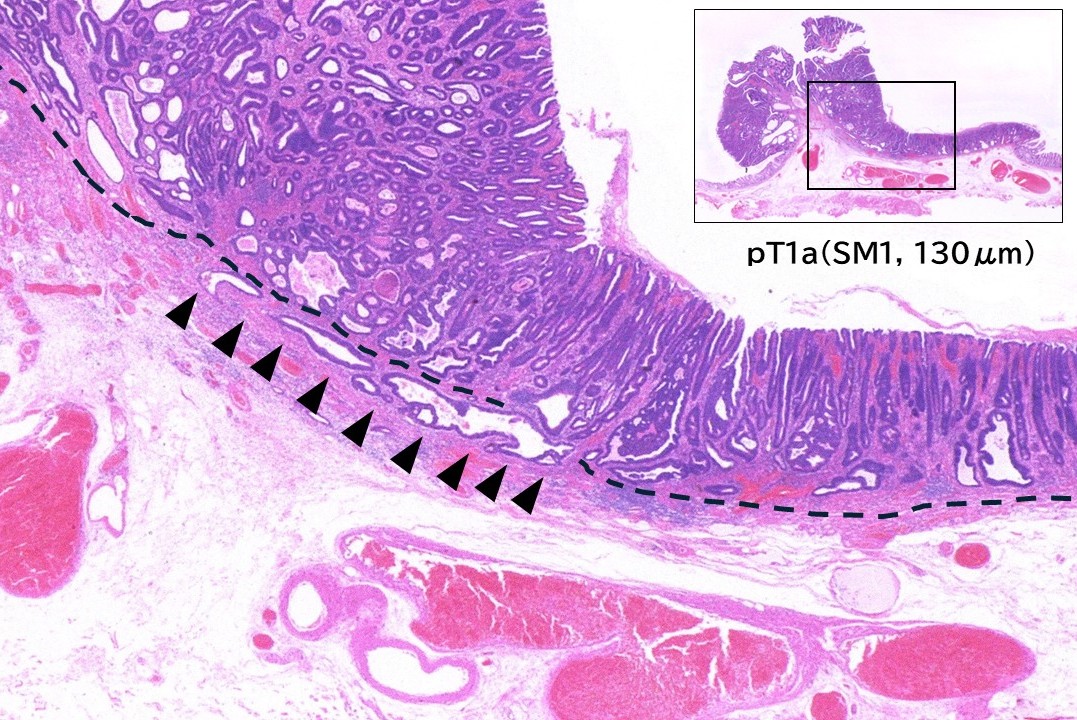

• 病理画像(ルーペ像)

図10

病変の内視鏡診断は早期大腸癌(M~SM1)を疑うも、SM深部浸潤の可能性も否定できず、経肛門内視鏡的筋層切除術(PAEM)にて一括切除した。病理組織学的診断は、Well differentiated tubular adenocarcinoma (tub1), pT1a(SM1), BD1, ly0, v0, HM0, VM0.であった。

• 病理画像(弱拡大像)

図11

切除標本(別切片)の弱拡大像:病変は隆起の基部でわずかにSM浸潤をきたしており、SM浸潤距離は130μmであった(矢頭)。